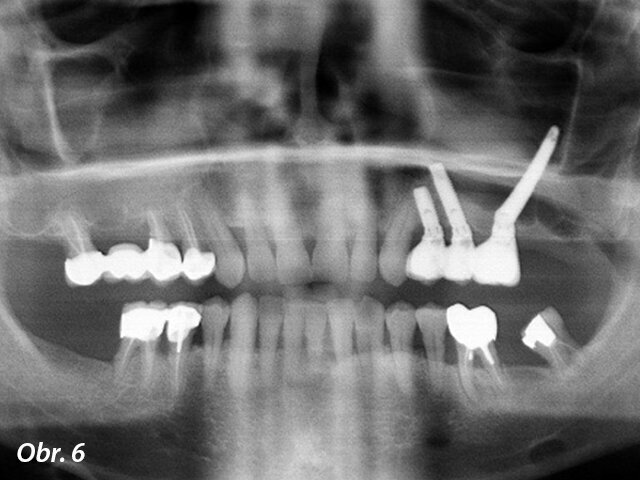

Předoperační RTG: dva premoláry a třetí molár v levé části maxily musely být extrahovány a pod čelistní dutinou nebylo dostatek kosti umožňující zavedení implantátů.

Muž, 56 let se k nám dostavil k rehabilitaci jeho částečně bezzubé levé horní čelisti, stěžoval si na neefektivní žvýkání. Zuby 26 a 27 byly extrahovány a nebyly nahrazeny a zuby 24 a 28 byly viklavé. Zub 25 byl endodonticky ošetřen, ale s periapikálním nálezem. Tyto 3 zuby byly přetíženy se značnou resorpcí kosti a jejich prognóza byla beznadějná. Generalizovaná parodontitis byla stabilizovaná (obr. 1). Jako náhrada zubů 24 a 25 byly zavedeny dva cylindrické samozaváděcí implantáty (Brånemark System Mk IV TiUnite regular platform [RP], Nobel Biocare) v délce 10 a 15 mm a v průměru 4 mm a následně i 35 mm dlouhý zygomatický implantát do pozice 26. Provizorní nefunkční šroubovaná fixní částečná náhrada byla okamžitě spojena se všemi třemi implantáty díky dostatečnému zaváděcímu kroutivému momentu. Pro tuto šroubovanou fixní částečnou náhradu byly použity multi-unit abutmenty (MUA, Nobel Biocare) 3 mm 17°, 2 mm 17° a 3 mm rovný RP. Finální fixní částečná náhrada byla nasazena po 4 měsících hojení (obr. 2–6).